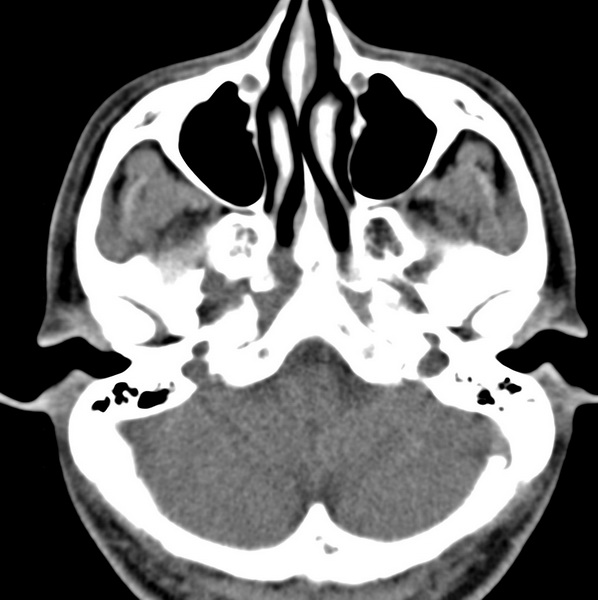

男、31、鼻咽部肿瘤放疗后请帮忙看看。

效果好,右侧破裂孔扩大,局部骨质缺损,为颅底骨质破坏。

1)鼻咽部肿瘤侵犯颅底放疗术后改变。2)左侧蝶窦炎。

咽后壁增厚,左侧咽鼓管隆突增大、咽鼓管咽口变浅,同侧咽旁间隙较窄。右侧颅底骨质破坏?为什么不在同一侧?

鼻咽部肿瘤侵犯颅底放疗术后改变.